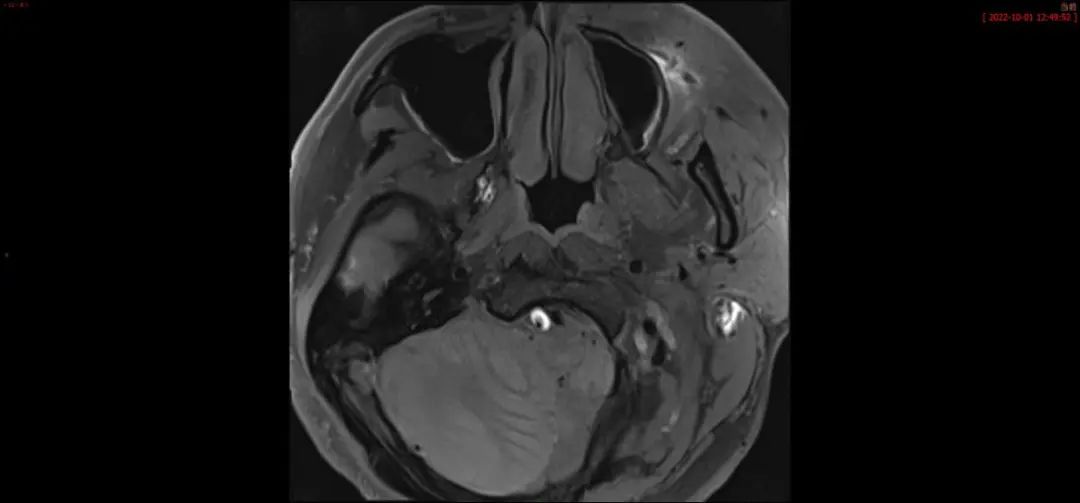

右侧椎动脉夹层